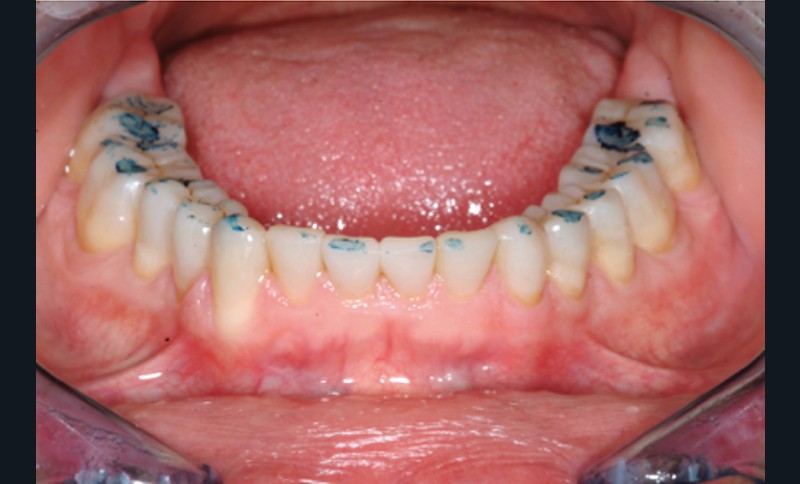

Jean-Pierre Attal : Tout à fait. Mais il faudra donner au prothésiste un maximum d’indications pour qu’il puisse réaliser sa cire de diagnostic. Vous découvrirez que la première étape de la réalisation de ces « full mock-up » est la réalisation d’un projet esthétique virtuel [8] à partir de cadrages photographiques précis aux trois échelles (visage, sourire, dento-gingivale). Gil Tirlet nous expliquera tout cela en détail avec des vidéos que j’ai déjà visionnées et qui sont très impressionnantes (fig. 1 à 4) !

Jean-Pierre Attal : Exactement, car il est possible d’appliquer le protocole de la technique « 3 steps » aux patients présentant des pertes de substance d’origine attritive (bruxisme) (fig. 5).